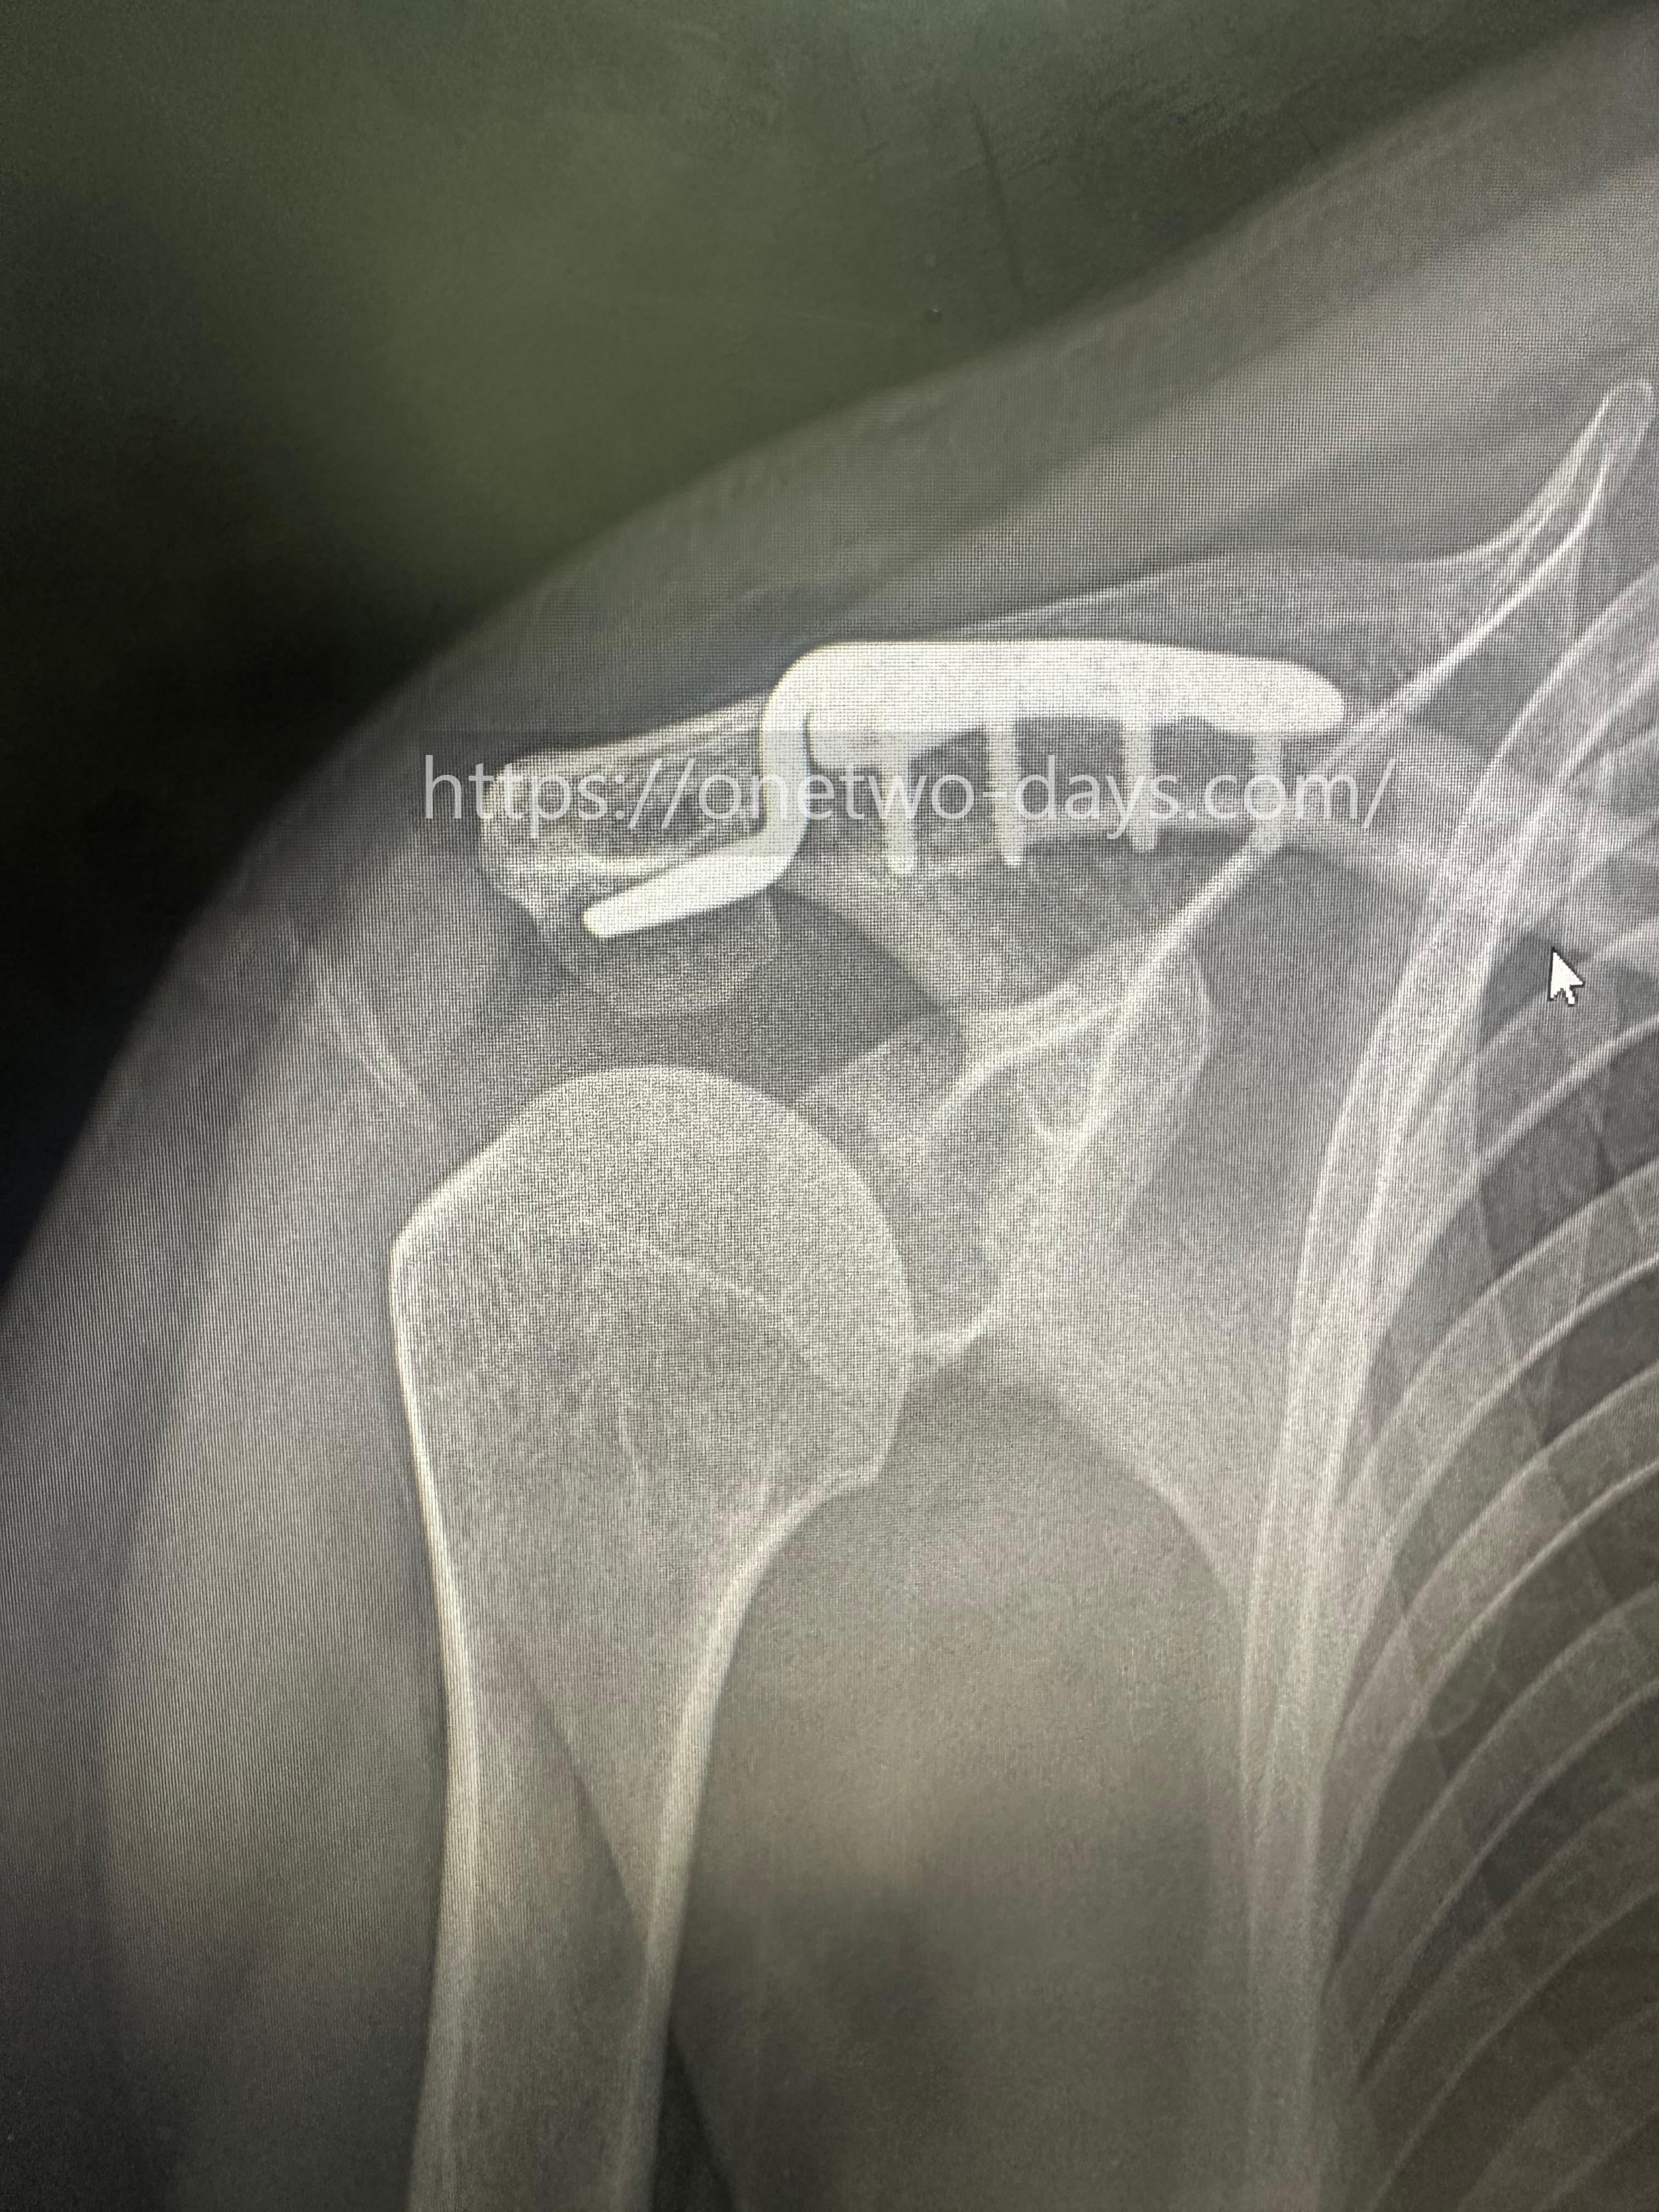

* 위 X-ray 사진은 실제 저의 어깨 X-ray 사진입니다.

이 사진에서 보이는 갈고리 모양이 후크 플레이트입니다. 어깨뼈와 쇄골 사이를 잡아주는 역할을 하지만, 움직일 때마다 주변 인대를 자극할 수 있어 제거가 필요합니다.

사진상으로 견쇄관절의 간격은 안정적으로 유지되고 있었으나, 내고정물(핀 또는 나사) 주변의 연부 조직이 회복되는 과정에서 약간의 간섭이 발견되었습니다. 이것이 제가 특정 각도에서 느꼈던 미세한 통증의 원인이었죠.

의사 선생님은 이 장치를 제거하고 주변 조직을 정리하는 2차 수술을 통해야만,

제가 원하는 '어느정도의 트레이닝 복귀'가 가능하다고 판단하셨습니다.